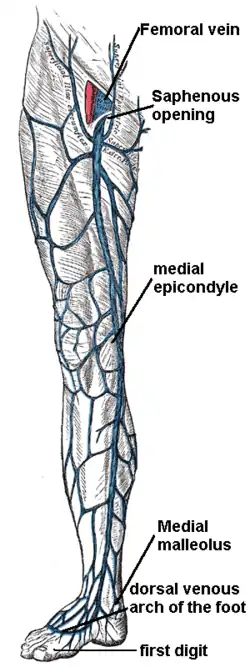

The great saphenous vein and landmarks along its course from the dorsal venous arch to the saphenous opening and femoral vein | |

The great saphenous vein (GSV) or long saphenous vein (/səˈfiːnəs/) is a large, subcutaneous, superficial vein of the leg. It is the longest vein in the body, running along the length of the lower limb, returning blood from the foot, leg and thigh to the deep femoral vein at the femoral triangle.

Structure

The great saphenous vein originates from where the dorsal vein of the big toe (the hallux) merges with the dorsal venous arch of the foot. After passing in front of the medial malleolus (where it often can be visualized and palpated), it runs up the medial side of the leg.[1] At the knee, it runs over the posterior border of the medial epicondyle of the femur bone. In the proximal anterior thigh 3–4 centimetres (1.2–1.6 in) inferolateral to the pubic tubercle, the great saphenous vein dives down deep through the cribriform fascia of the saphenous opening to join the femoral vein. It forms an arch, the saphenous arch, to join the common femoral vein in the region of the femoral triangle at the sapheno-femoral junction.[1]

Superficial veins of lower limb. Superficial dissection. Anterior view.

Superficial veins of lower limb. Superficial dissection. Anterior view. Great saphenous vein. Deep dissection. Anterior view.